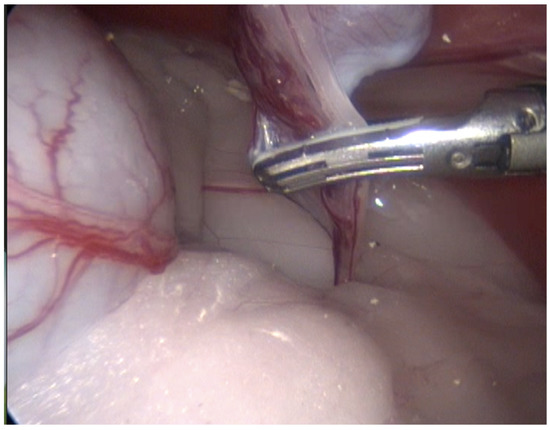

Figure 4.

Technique with three access ports. View of the maneuvers of the testis support with a grasping of forceps and coagulation and cutting of the vascular pedicle, spermatic cord, and gubernaculum, performed with a harmonic scalpel device. (See Supplementary Video S1 in Supplementary Materials.)

In 13 cases, the coagulation and cutting of the vascular pedicle, the spermatic cord, and the gubernaculum were performed with advanced electrothermal bipolar energy devices (eight with the Laparoscopic Tissue Sealer G2-ENSEAL® Ethicon-Johnson & Johnson (New York, NY, USA) and five with LigaSureTM Covidien-Medtronic (Dublin, Ireland), https://www.jnjmedtech.com/global, https://www.medtronic.com/covidien/en-us/index.html accessed on 27 October 2022) (Figure 3). In five cases, this procedure was made with a Harmonic scalpel device (Figure 4 and Supplementary Video S1) (Harmonic ACE® +Shears and Gen11 generator Ethicon-Johnson & Johnson), and in one case, with the use of a monopolar energy hook.

The following supporting information can be downloaded at: https://www.mdpi.com/article/10.3390/ani13010181/s1, Video S1: Technique with three access ports. View of the manoeuvres of the testis support with a grasping forceps and coagulation and cutting of the vascular pedicle, spermatic cord, and gubernaculum, performed with a harmonic scalpel device.